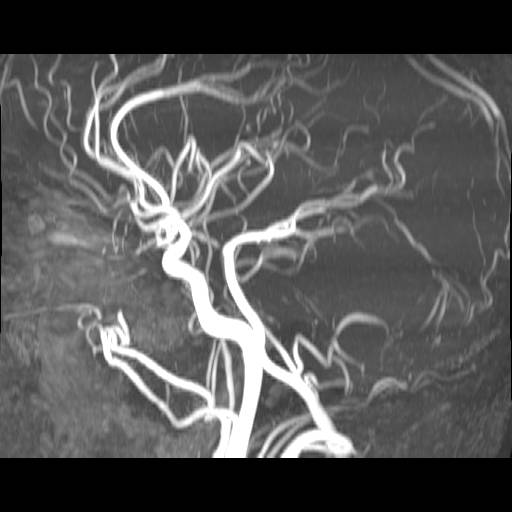

Hjerne, Normal, MR-angiografi

Normal karundersøgelse (angiografi) af hjernen.